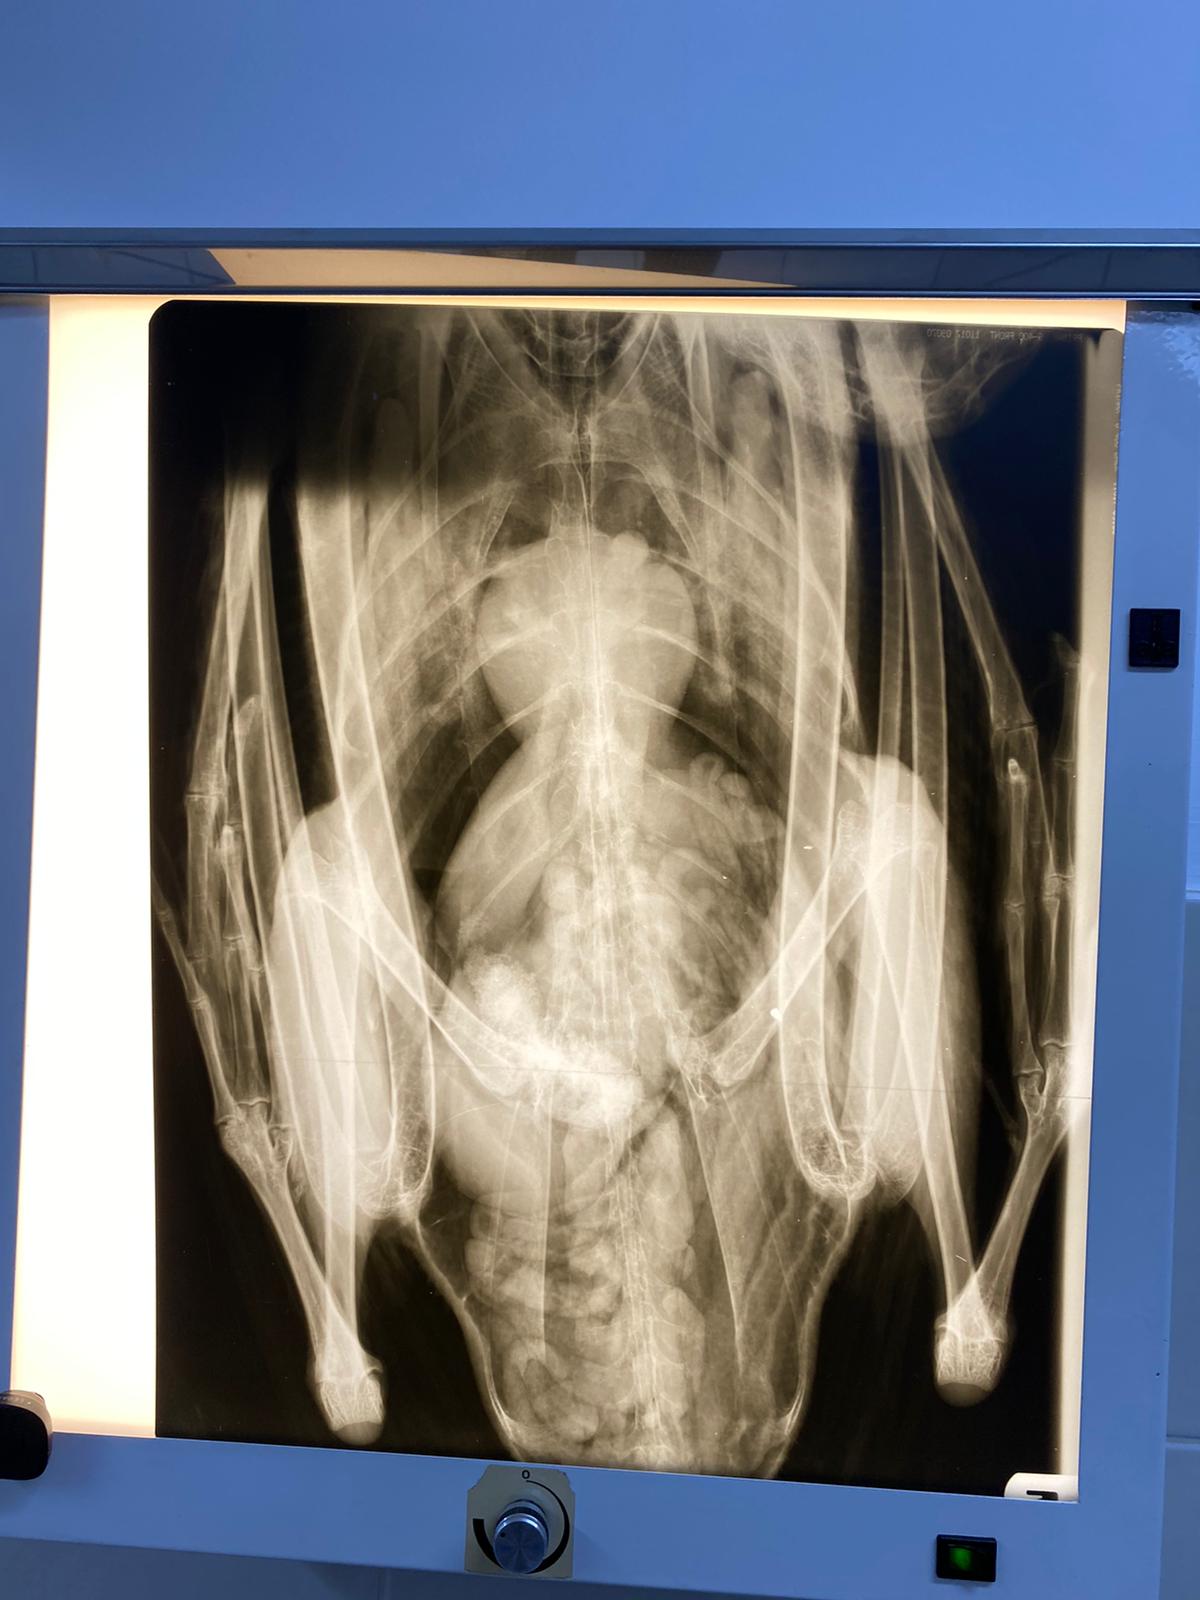

Împreună cu reprezentantul AJVPS Botoșani (Ajvps BT Vanatoare Pescuit) au preluat exemplarul de lebadă si l-am încredințat în custodie provizorie, până la atingerea stării fiziologice normale, cabinetului veterinar

Trio.vet coordonat de dr. Daniel Bejinariu și dr Dănuț Bratu.

Starea de sănătate a lebedei a fost evaluată (tulburări nervoase, în urma unor traumatisme la nivelul capului), fiind în continuare sub observație și tratament. După însănătoșire lebăda va fi eliberată în habitatul natural sau încredințată unei asociații care se ocupă cu îngrijirea păsărilor migratoare sau unei alte entități specializate în protejarea animalelor și păsărilor.